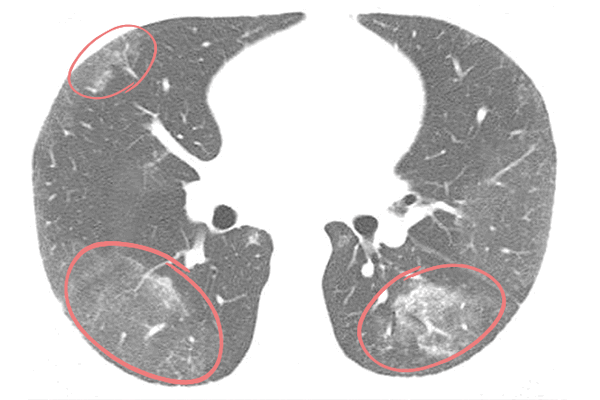

Намного информативнее компьютерная томография. Она позволяет обнаружить злокачественную опухоль, оценить ее размеры, локализацию, тип, степень и протяженность обструкции, состояние соседних анатомических структур, проходимость дыхательных путей ниже места сужения. С помощью КТ можно выявить спадение легкого (ателектаз, коллапс), пневмонию и правильно спланировать лечение.

Симптомы опухолей бронхов

Наиболее яркая клиническая симптоматика развивается при эндобронхиальном росте опухоли, вызывающей нарушение бронхиальной проходимости. На стадии частичного бронхостеноза диаметр просвета бронха практически не изменен, пациента может беспокоить раздражающий кашель с небольшим количеством мокроты, изредка - кровохарканьем. Общее самочувствие не страдает. Рентгенологические признаки опухолевого роста отсутствуют; выявление новообразования возможно только с помощью КТ легких или бронхоскопии.

На стадии клапанного стеноза бронха опухоль уже в значительной мере перекрывает просвет воздухоносных путей. Больного беспокоит постоянный кашель с выделением слизисто-гнойной мокроты, кровохарканье, одышка, свистящее дыхание. Во время выдоха под давлением опухоль может полностью закрывать бронх, в связи с чем на этом этапе возникают признаки нарушения легочной вентиляции, воспалительные изменения. Рентгенологически обнаруживаются сегментарные инфильтраты, опухоль бронхов подтверждается эндоскопически или с помощью линейной томографии.

Полная обтурация бронха опухолью приводит к формированию ателектаза, нагноительных процессов в невентилируемом участке легочной ткани. Клиническая картина соответствует обтурационной пневмонии: лихорадка, кашель с гнойной мокротой, общая слабость, потливость. При аррозии бронхиальных сосудов могут возникать массивные легочные кровотечения.

Как правило, первым шагом на пути выявления опухоли бронха является рентгенография легких в двух проекциях и томографическое исследование. В большинстве случаев рентгенологически определяется гиповентиляция или ателектаз части легкого; на томограммах - "ампутация" обтурированного опухолью бронха. Для оценки васкуляризации опухоли бронха целесообразно выполнение бронхиальной артериографии или ангиопульмонографии.